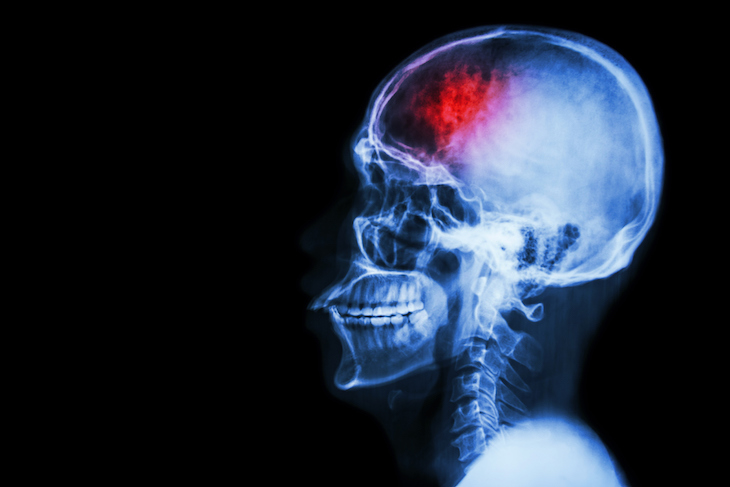

After seeing my scans, the doctor in Colombo explained that I had had a minor stroke on the right side of my brain and another, more significant, at the back, in an area dealing with speech and memory. Had I been in the UK, I realised sadly, I might not have had the second one, because the hospital would have taken action after the first.